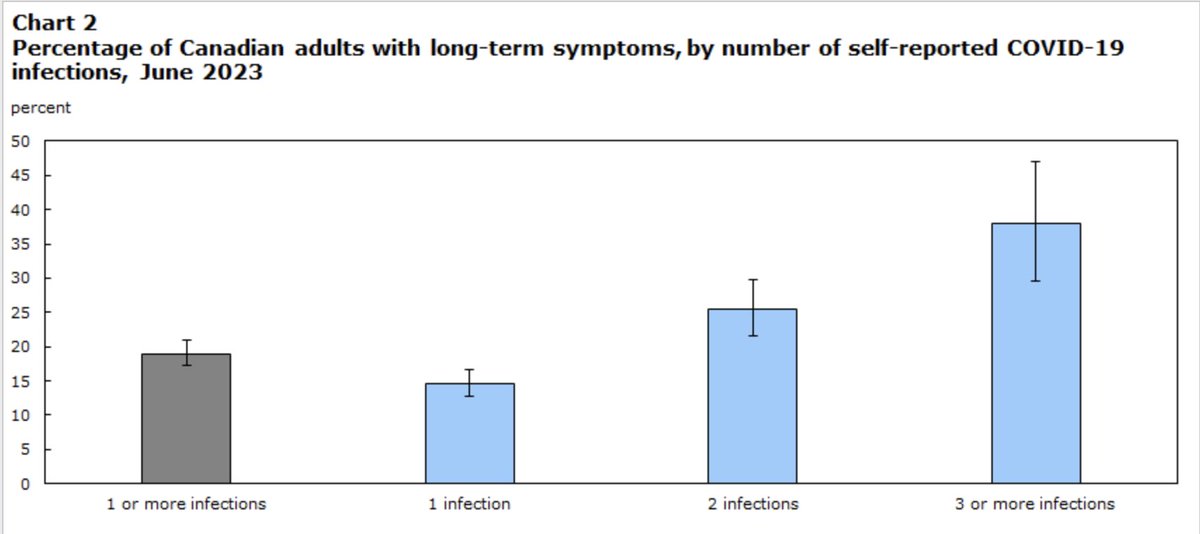

Two things many still don’t understand:. 1. SARS-CoV-2 causes a vascular, multisystemic illness & damages the immune system. 2. Damage can be cumulative, & it may take several “hits” before onset of #LongCovid. This is why you see people who were “fine” now in poor health.

As we wrote @ScienceMagazine. "Each reinfection contributes additional risk of #LongCovid: Cumulatively, two infections yield a higher risk of Long Covid than one infection, and three infections yield a higher risk than two infections"—@zalaly and me. The